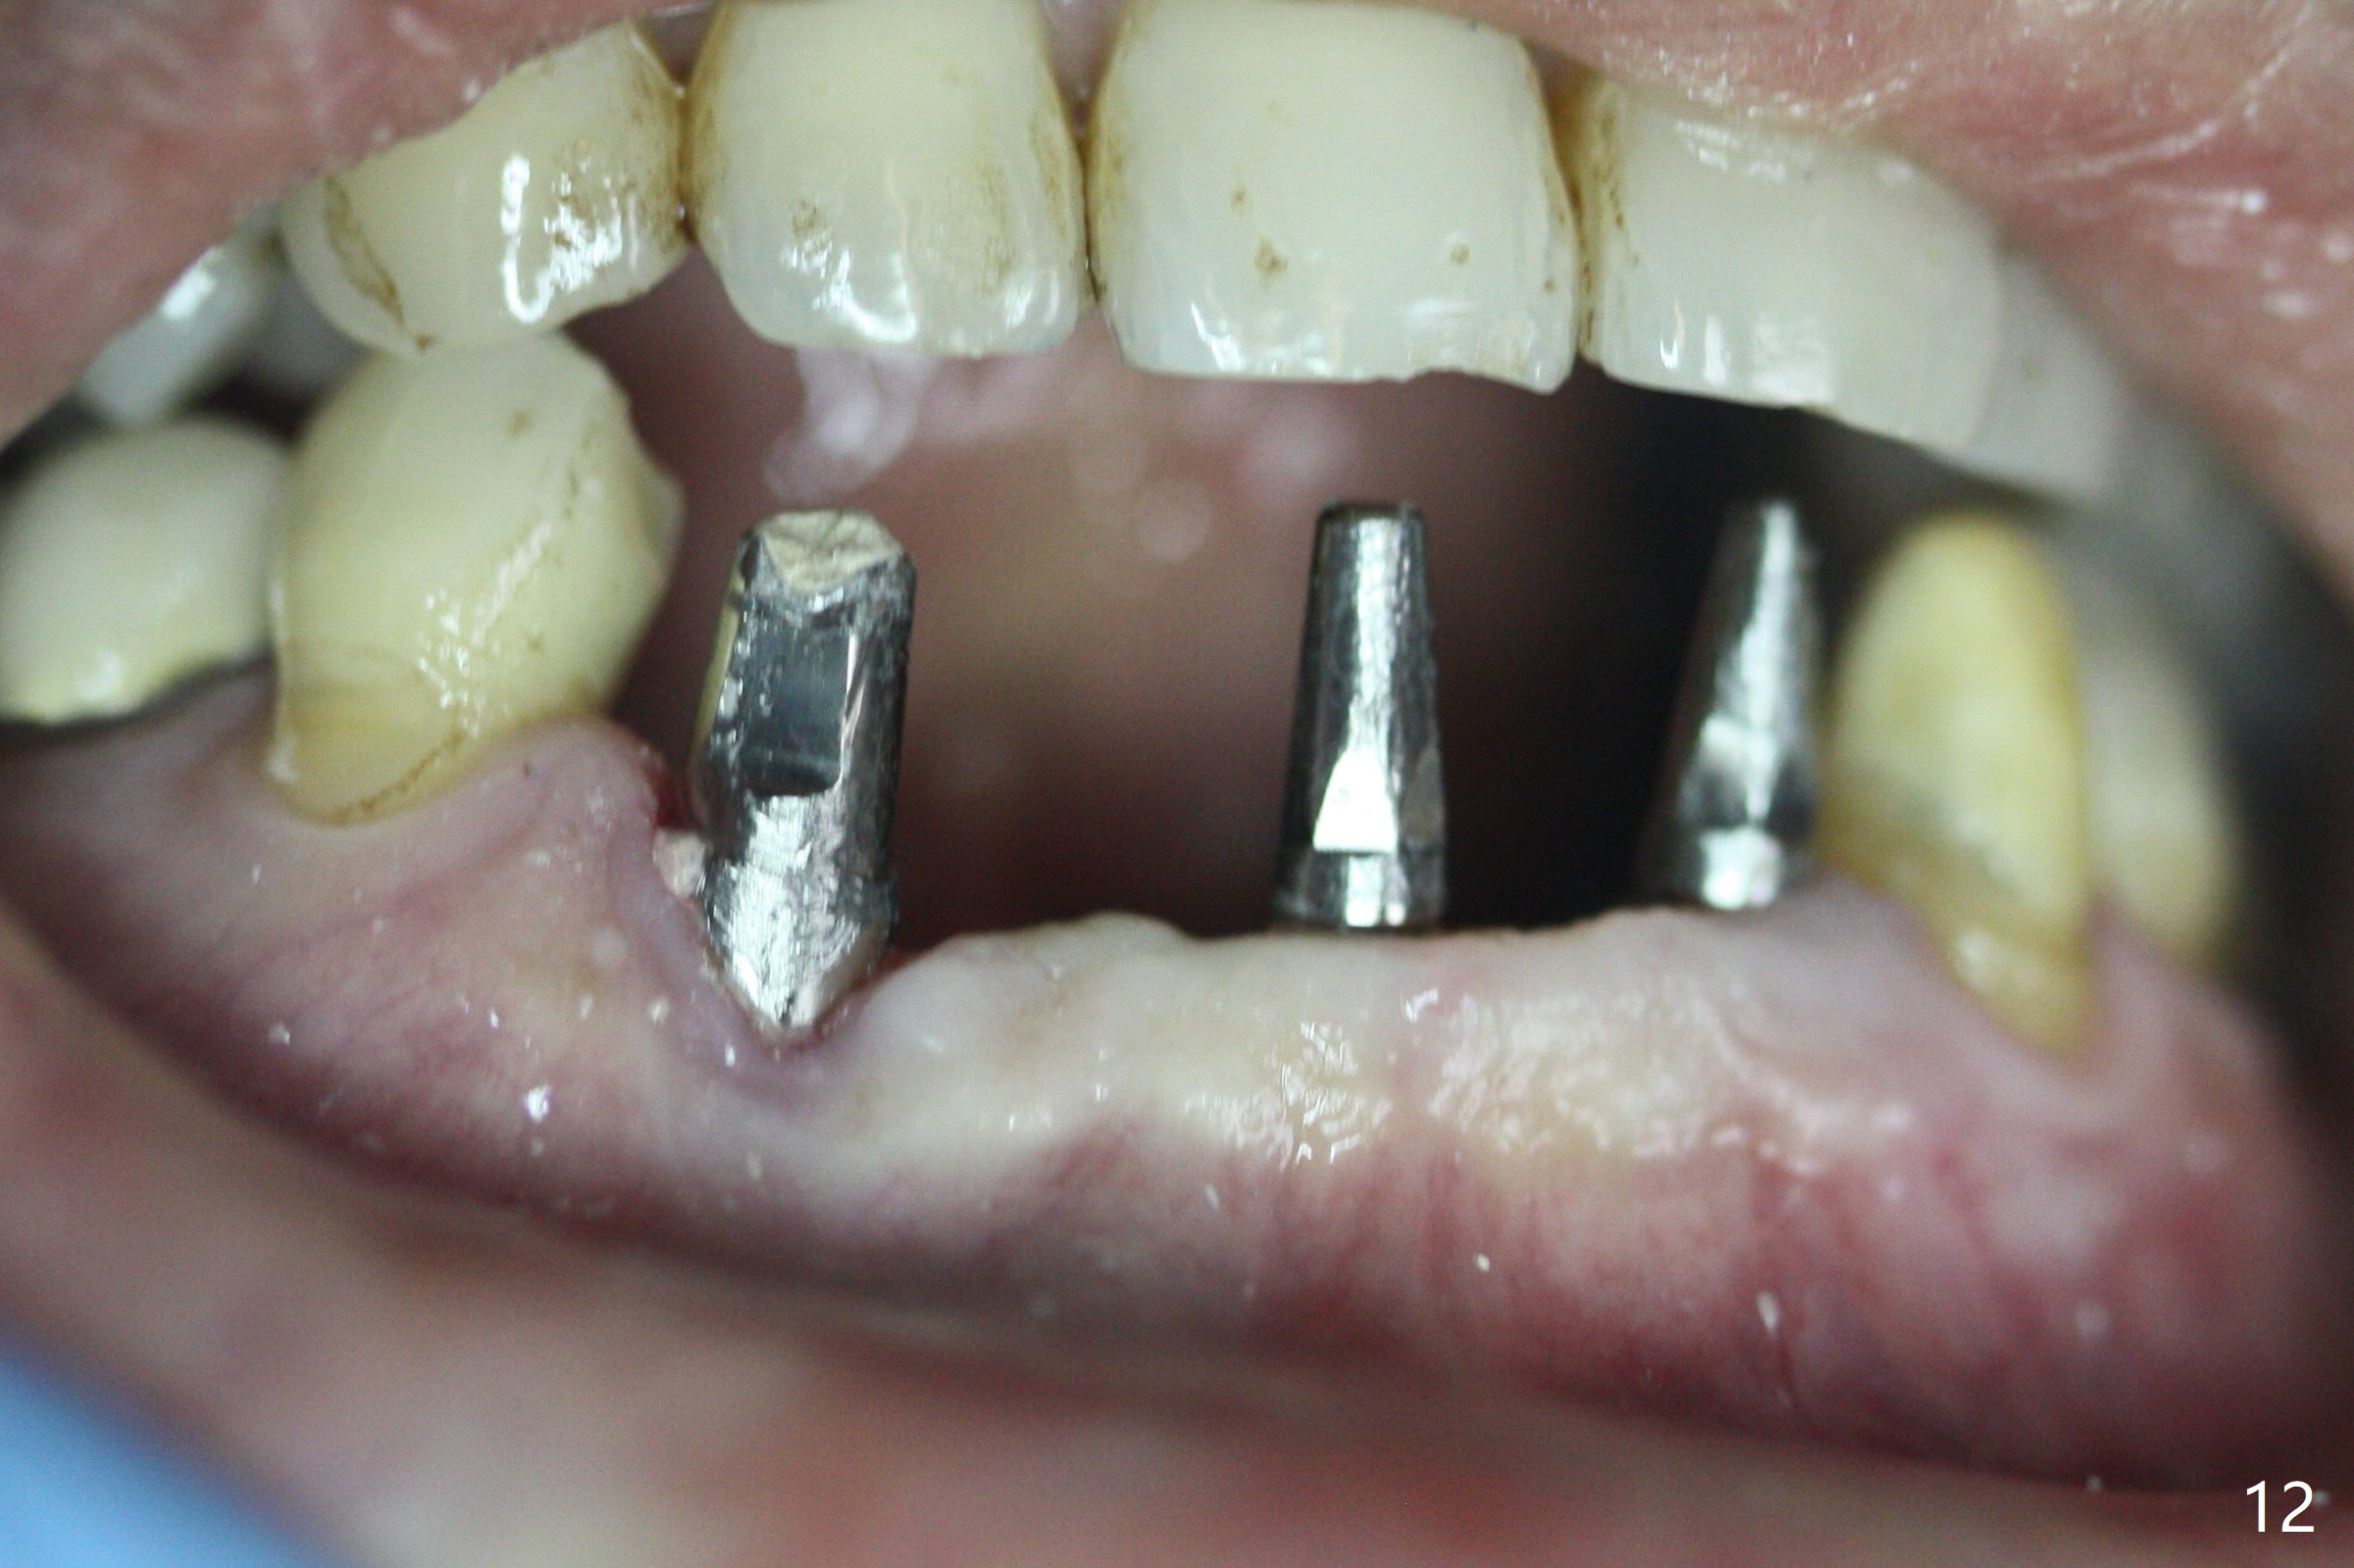

The mesial defect at #27 appears to have been repaired 8 months postop (Fig.8,9 *); there is no bone loss at 1-piece implant sites. The gingival recession seems to remain the same before and after removal of the provisional FPD (Fig.10,11). The bulging abutment at the cervix is less prominent when a straight abutment is used and prepared (Fig.12, 4.5x5.5(5) mm). There is no bone loss at #23, 25 and 27 sites 2.5 years post cementation (Fig.12-15), although the trajectory of the implants could be improved by using surgical guide (Fig.16-18).